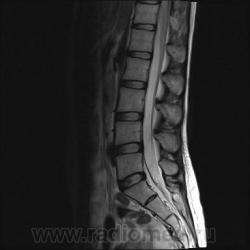

Пациентка 25 лет обратилась к неврологу с жалобами на слабость, изменение походки. Раньше не обследовалась.

С подавлением сигнала от жира:

Я специально сделал изображения потемнее, чтобы выделить патологию (жировую дегенерацию) именно мышечной ткани.

Гм, как это я пропустил эту публикацию. Поясничные мышцы замещены жировой тканью; т.е. Они выглядят "белыми" на Т1 и Т2, в последовательности с подавлением жира, соответственно сигнал уходит; и они "тёмные". Такую картину я видел у пожилых, иногда у пациентов после операции на позвоночнике. По поводу болезни Штейнерта, должна быть клиника, изменения и гипотония/атония мышц других локализаций. На основании только МРТ ПОП не совсем убедительно. Вот небольшая ознакомительная статейка.